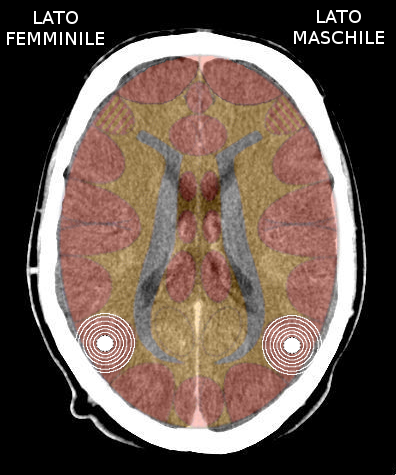

- Requisiti: Si è in costellazione schizofrenica quando due attivazioni colpiscono i due emisferi cerebrali di uno stesso livello:

- le due emiparti del tronco cerebrale;

- i due emisferi cerebellari;

- i due emisferi cerebrali (midollo e/o corteccia).

- NON È COSTELLAZIONE quando due attivazioni interessano due livelli cerebrali differenti, anche se occupano i due emisferi.